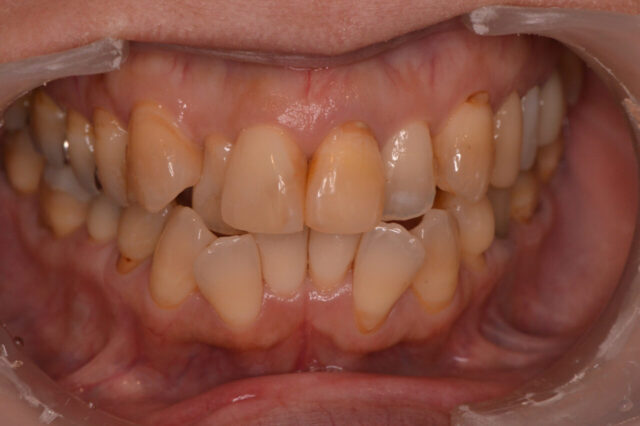

性別 女性 主訴 「前歯の色が気になる」「できれば削らずにきれいにしたい」というご相談で来院されました。 治療 診査の結果、前歯には失活歯による内部からの変色(いわゆる黒ずみ)が認められました。

通常であれば、ラミネートベニアやセラミッククラウンによる修復が検討されるケースです。

しかし本症例では、歯質の保存を最優先に考え、以下の治療を選択しました。

インターナルブリーチ(ウォーキングブリーチ)による内部漂白

色調改善後にダイレクトボンディングによる形態・色調修正

まず歯の内部に漂白剤を作用させることで、歯質自体の明度を改善。

その後、周囲の歯との色調バランスを考慮しながらコンポジットレジンにて微調整を行いました。

結果として、歯を大きく削ることなく、自然で調和のとれた前歯の審美性を回復することができました。料金 1本10万円+tax 備考 本症例のポイントは、「削らない選択肢」を最大限活かした点にあります。